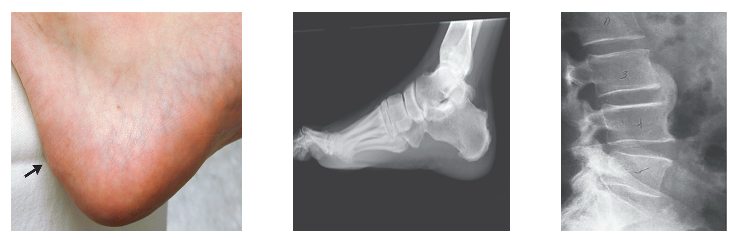

Enthesitis/enthesopathy

*LOB: Describe patterns of joint disease using appropriate terminology (e.g. monoarthritis, oligoarthritis, polyarthritis) and identify common causes for these patterns

A

First stage in ankylosing spondylitis

Inflamation of the enthesis

Enthesis is the site where a tendon inserts into a bone

Symptoms: pain swelling and inflamation in the peripheral joints